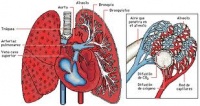

Los pulmones. Son órganos esenciales del aparato respiratorio, es el sitio en que se verifican las importantes funciones de la hematosis. En ellos la sangre recibe oxígeno desde el aire y a su vez la sangre se desprende de dióxido de carbono el cual pasa al aire. Este intercambio, se produce mediante la difusión del oxígeno y el dióxido de carbono entre la sangre y los alvéolos que forman los pulmones.

Los pulmones estas constituidos por los lobulillos pulmonares que se continúan con los bronquiolos y bronquios intra pulmonares, también está formado por el tejido conjuntivo que une lobulillos, vasos y bronquiolos.

Lobulillos pulmonares. Son pequeños sacos membranosos, pegados entre si y unidos por escaso tejido conectivo. Tienen un volumen de un centímetro cúbico.

Son piramidales en la periferia, constituyendo campos poligonales visibles en la superficie exterior de los lóbulos, son más ovoides en el interior del órgano. Por una de sus extremidades se continúan con el bronquio supralobulillar, que le es aferente. Jamás se comunican entre sí; en un lobulillo examinado aisladamente se observa que el bronquio supralobulillar continua en el lobulillo (bronquio intralabulillar), emitiendo primero colaterales y bifurcándose después.

Colaterales o ramas de bifurcación terminales se subdividen dicotómicamante en cierto número (veinte a treinta) ramificaciones terminales, cada una de las cuales termina en un ácino y se llaman bronquiolos acinosos. Los cortes practicados a diferentes alturas presentan, ya el bronquiolo intralobulillar, ya un número de colaterales que varía según la altura del punto observado . Cada ácino, que tiene de 1 a 2 milímetros, presenta, después del estrechamiento del bronquiolo, una dilatación (vestíbulo), de la cual parten cuatro o cinco conductos alveolares, que terminan en cavidades más vastas, laterales o terminales, con relación al eje del ácino, los infundíbulos. Tanto los conductos alveolares como los infundíbulos están tapizados de celdillas semejantes a las de un panal de Abejas, los alvéolos (250 por un milímetro cúbico de pulmón). La superficie pulmonar, calculada de este modo, viene a representar por término medio una superficie de 80 metros cuadrados.

Cada alveolo se compone de pared y epitelio. La pared delgada, transparente, está reforzada exteriormente por un sistema de fibras elásticas, cuya disposición es variable.

Vasos. El lobulillo presenta vasos sanguíneos y linfáticos. La arteria pulmonar envía, un vaso que se adosa al bronquiolo intralobulillar (arteria lobulillar), ramificándose con él. Al llegar al ácino, las últimas ramificaciones se esparcen por la superficie del alvéolo en forma de red muy apretada de capilares muy finos y de carácter terminal. Las venas que siguen a estos capilares se dirigen a la periferia del lobulillo (venas perilobulillares), para constituir por su reunión las venas pulmonares. Los linfáticos de origen lobulillar mal determinado, alcanzan los espacios interlobulillares. Los nervios terminan en la pared de los alvéolos.

La función de los pulmones es realizar el intercambio gaseoso con la sangre, por ello los alvéolos están en estrecho contacto con capilares. En los alvéolos se produce el paso de oxígeno desde el aire a la sangre y el paso de dióxido de carbono desde la sangre al aire. Este paso se produce por la diferencia de presiones parciales de oxígeno y dióxido de carbono (difusión simple) entre la sangre y los alvéolos.

Anatomía funcional

El pulmón de mamífero está constituido por multitud de sacos adyacentes llenos de aire denominados alvéolos. Se hallan interconectados unos con otros por los llamados poros de Kohn, que permiten un movimiento del aire colateral, importante para la distribución del gas. Los conductos aéreos del pulmón, que no intervienen en la función respiratoria, están formados por cartílago y músculo liso. El epitelio es ciliado y secreta un mucus que asciende por el conducto respiratorio y mantiene todo el sistema limpio!